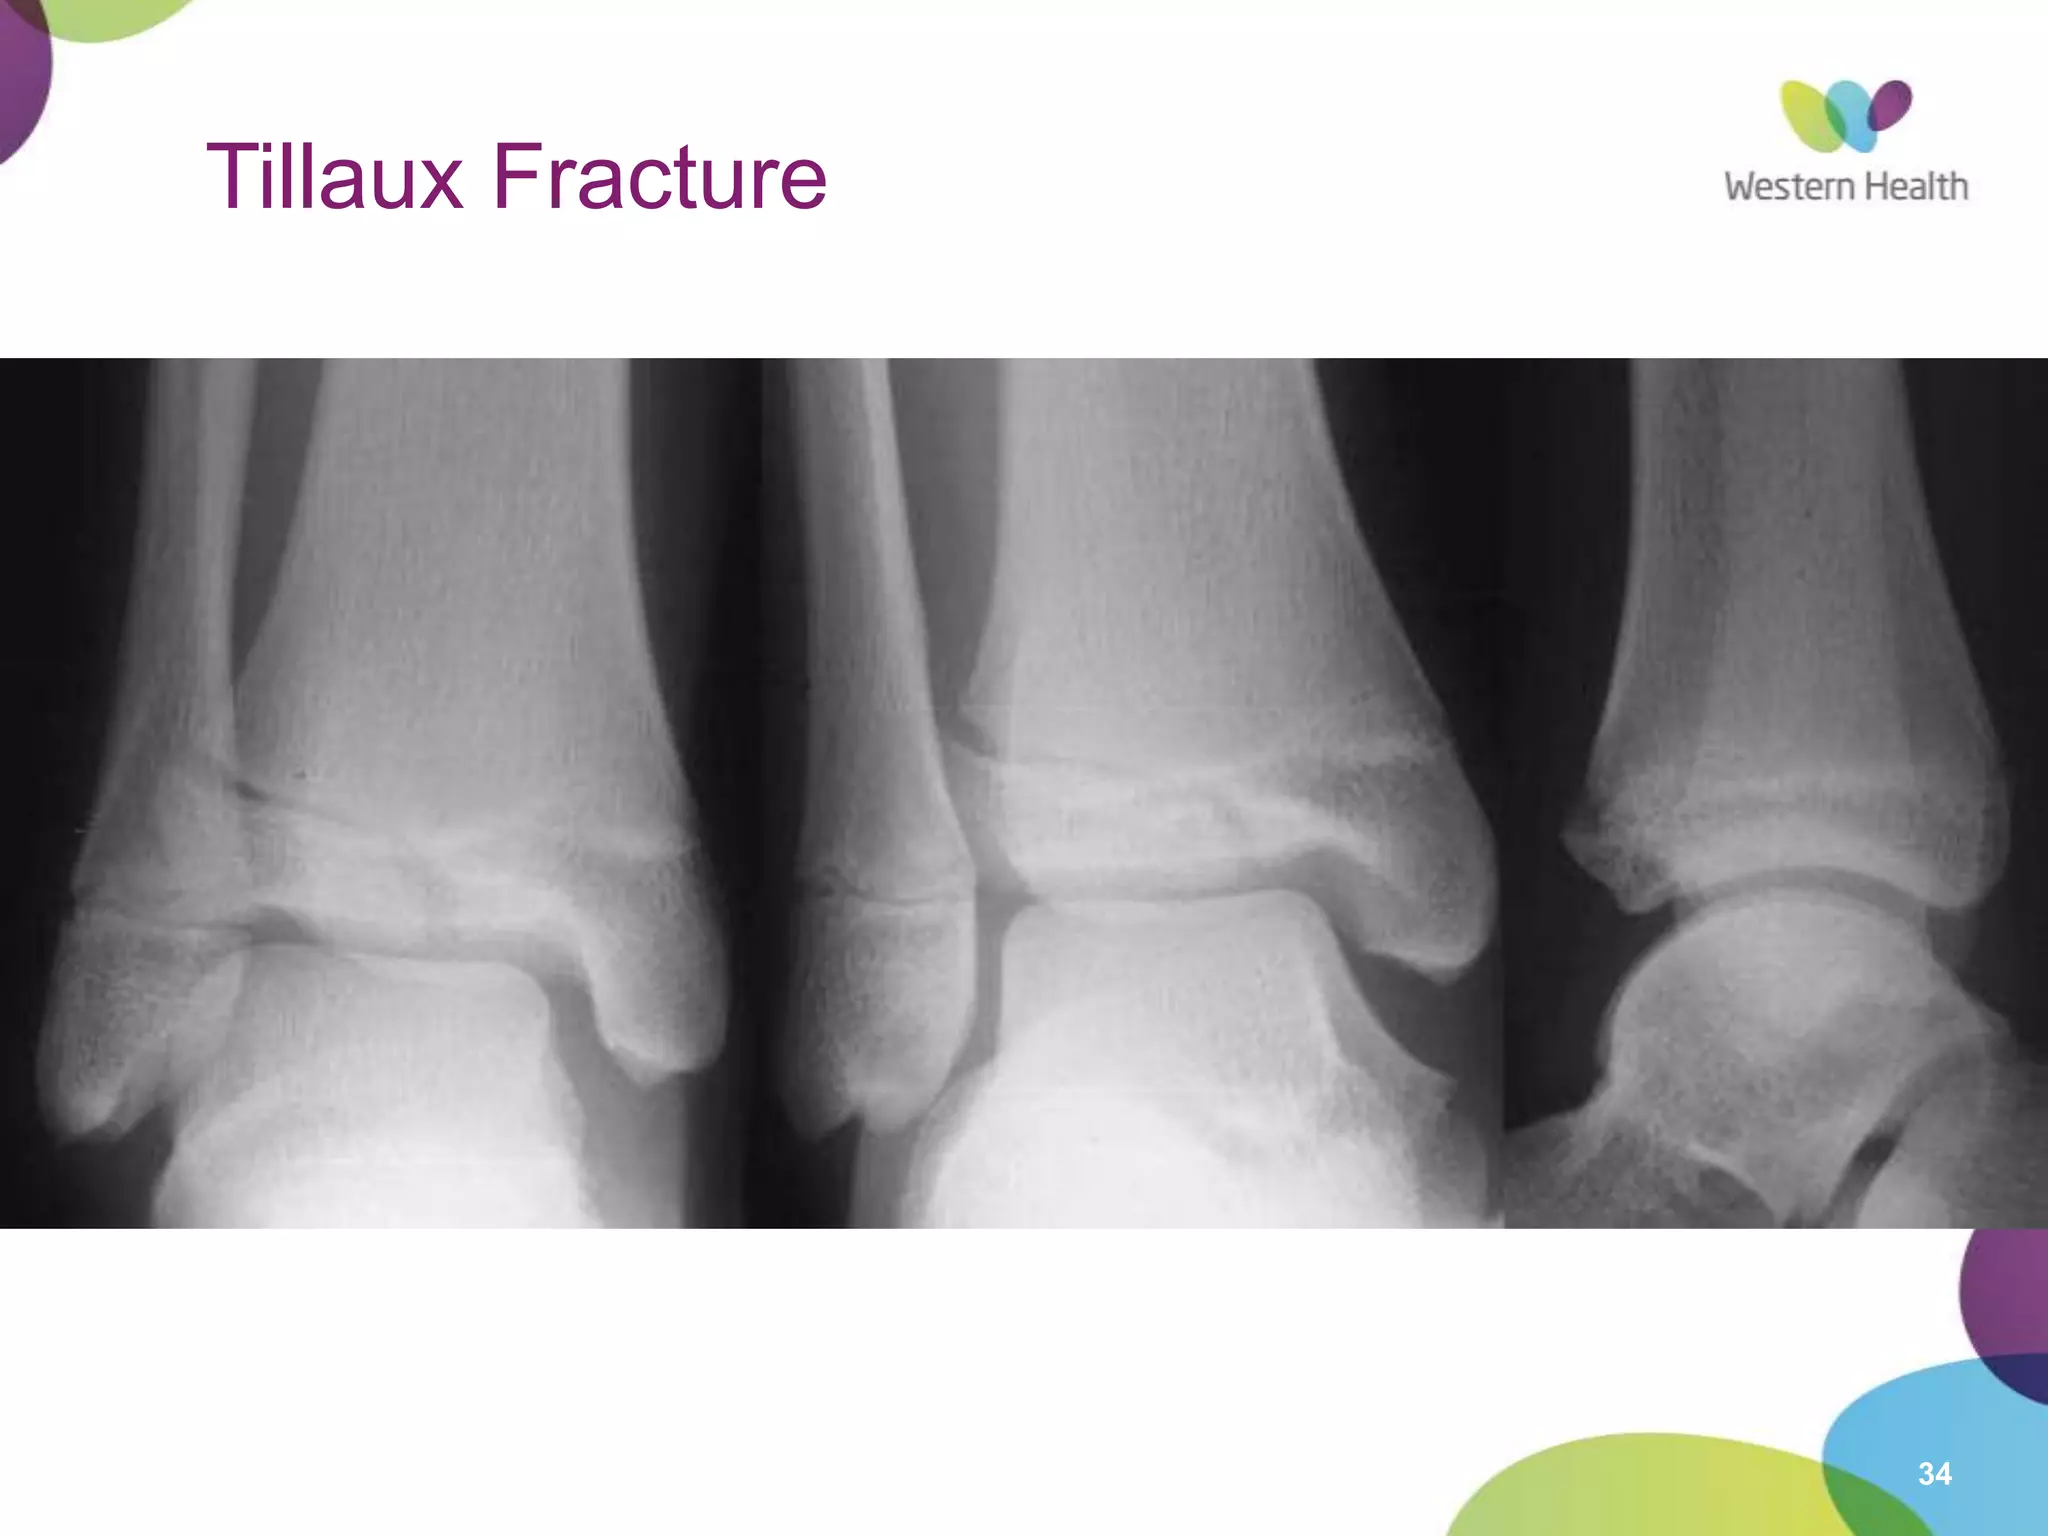

Tillaux Fracture

• Occurs in 12-14 year olds

18 month period when epiphysis is closing

• Salter-Harris 3 injury

Runs through anterolateral physis until reaches fused part, then

extends inferiorly through epiphysis into joint

Visible if x-ray parallel to plane of fracture (may require oblique)

• Mechanism

External rotation

Strenth of tibiofibular ligament > unfused epiphysis

Strenth of tibiofibular ligament > unfused

epiphysis

• Management

Articular injury

Gap >2mm in articular surface

= ORIF

Non-displaced

• NWB below knee cast

Displaced

• surgery